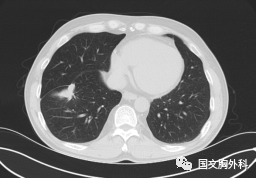

這個病人檢查胸部CT如圖3:根據(jù)影像學(xué)考慮是惡性腫瘤,行手術(shù)治療后病理回報(bào):“肺膿腫,合并炎癥纖維組織增生”,因此“肺占位”不代表就是惡性腫瘤,診斷金標(biāo)準(zhǔn)是病理診斷。如果檢查后發(fā)現(xiàn)“肺占位”先不要驚慌,及時(shí)就診請專科醫(yī)生會診指導(dǎo)治療才是關(guān)鍵。